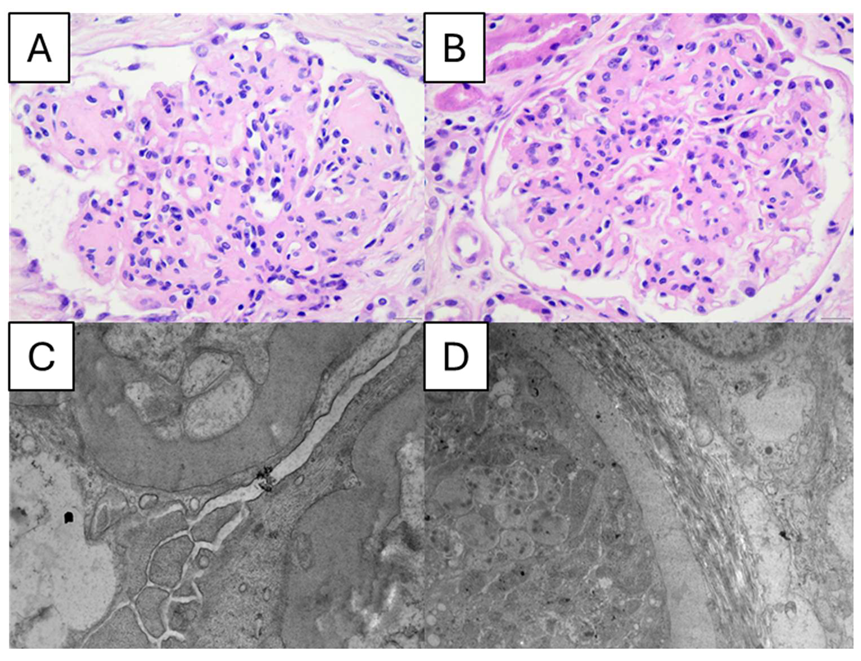

- Tervaert, T.W.C.; Mooyaart, A.L.; Amann, K.; Cohen, A.H.; Cook, H.T.; Drachenberg, C.B.; Ferrario, F.; Fogo, A.B.; Haas, M.; de Heer, E.; et al. Pathologic Classification of Diabetic Nephropathy. J. Am. Soc. Nephrol. 2010, 21, 556–563. [Google Scholar] [CrossRef] [PubMed]

| Glomerular | Interstitial and Vascular | ||||||||

![]() | ![]() | ||||||||

| I | IIa | IIb | III | IV | Interstitial lesions. | Interstitial inflammation. | Vascular lesions arteriolar hyalinosis. | Presence of large vessels. | Arteriosclerosis (score worst artery). |

| Mild or nonspecific LM changes and EM-proven GBM thickening. | Mild mesangial expansion. | Severe mesangial expansion. | Nodular sclerosis (Kimmelstiel– Wilson lesion). | Advanced diabetic glomerulosclerosis. | No IFTA 25% 25% to 50% 50% | Absent 0. Infiltration only in relation to IFTA 1. Infiltration in areas without IFTA 2. | Absent 0. At least one area of arteriolar hyalinosis 1. More than one area of arteriolar hyalinosis 2. | Yes/no | No intimal thickening 0. Intimal thickening less than thickness of media 1. Intimal thickening greater than thickness of media 2. |

| Biopsy does not meet any of the criteria mentioned below for class II, III, or IV. GBM 395 nm in female and 430 nm in male individuals 9 years of age and older. | Biopsy does not meet criteria for class III or IV. Mild mesangial expansion in 25% of the observed mesangium. | Biopsy does not meet criteria for class III or IV. Severe mesangial expansion in 25% of the observed mesangium. | Biopsy does not meet criteria for class IV. At least one convincing Kimmelstiel– Wilson lesion. | Global glomerular sclerosis in 50% of glomeruli. Lesions from classes I through III. | |||||